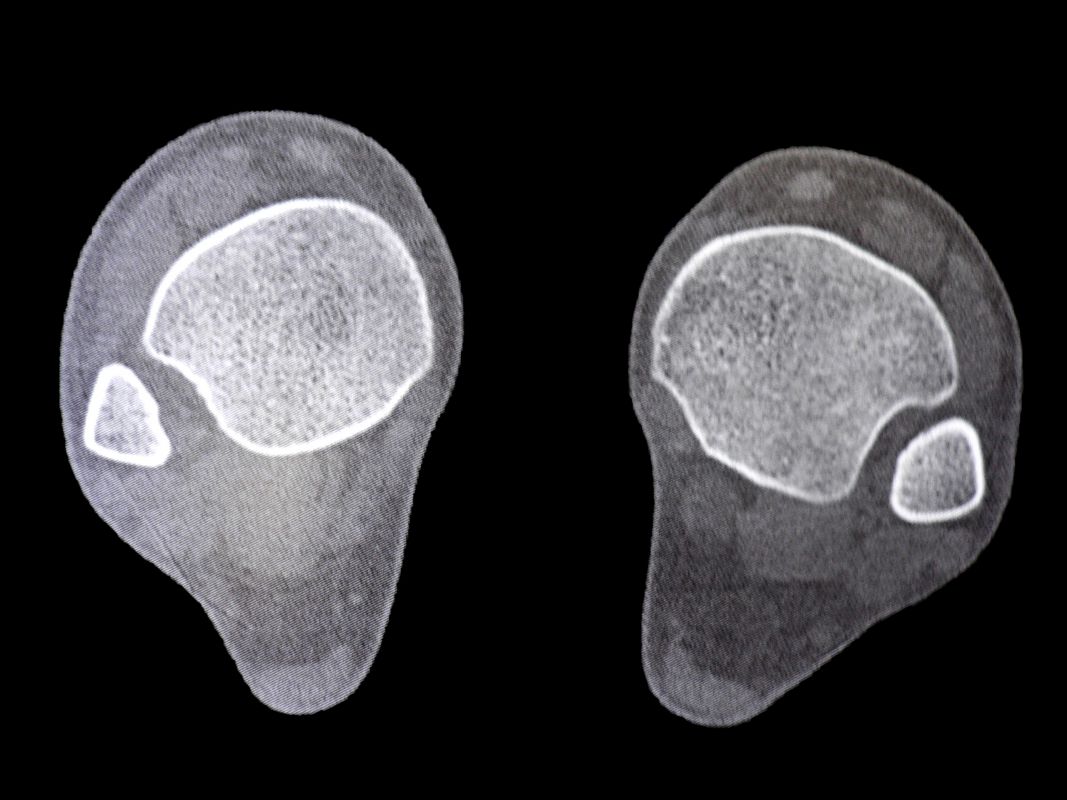

Computertomographie (CT)

Die CT-Diagnostik erlaubt eine kritischere Beurteilung des DTFG. Die Wertigkeit zur Beurteilung von Syndesmosenverletzungen wurde in diversen Studien untersucht. Die Kongruenz im distalen Tibiofibulargelenk sollte in den axialen Schichten beurteilt werden 39. Aufgrund der hohen physiologischen Varianz, ist ein Seitenvergleich empfehlenswert (Abb. 5). So können die anteroposteriore Translation, Rotation und Verkürzung des betroffenen DTFG im Vergleich zum gesunden DTFG verglichen werden 40.